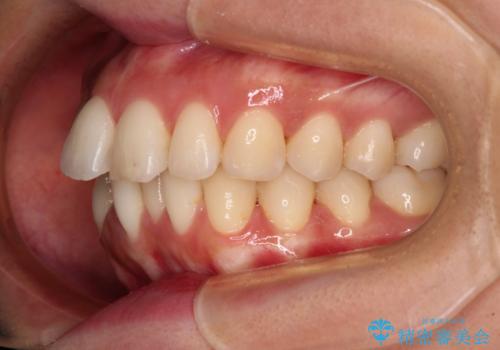

舌の突出癖がなかなか改善されず、上下前歯の接触がやや甘い状態での仕上がりとなりました。

接触が甘い場合、上顎前歯の叢生が後戻りを起こしやすくなるため、治療終了後の保定期間でも舌のトレーニングを継続するように指示しています。